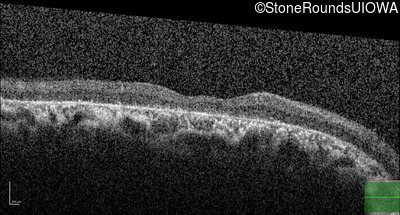

Optical Coherence Tomography - Left - 20/32

Exemplar / OCT Stack